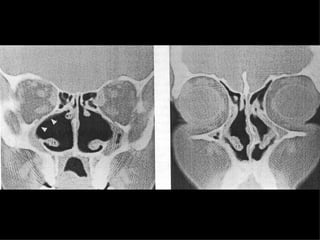

Radiographic Findings Mucoperiosteal thickening of the paranasal sinuses. Loss of definition of the OMC secondary to resorption of the ethmoid bulla and uncinate process. Hypoplasia of the maxillary sinuses. Enlargement of the nasal cavities with erosion and bowing of the lateral nasal wall. Bony resorption and mucosal atrophy of the inferior and middle turbinates. Pace-Balzan, Shankar, Hawke. J Otolaryngol 1991; 20:428-32.

Radiographic Findings Mucoperiostealthickening of the paranasal sinuses. Loss of definition of the OMC secondary to resorption of the ethmoid bulla and uncinate process. Hypoplasia of the maxillary sinuses. Enlargement of the nasal cavities with erosion and bowing of the lateral nasal wall. Bony resorption and mucosal atrophy of the inferior and middle turbinates. Pace-Balzan, Shankar, Hawke. J Otolaryngol 1991; 20:428-32.